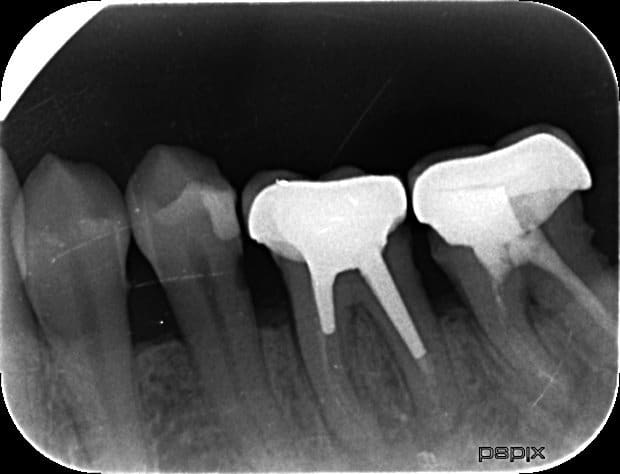

Bonjour, patiente qui a de temps en temps des douleurs sur 36 et qui me dit avoir déjà eu un abcès.

Au vu de la présence d'un inlay core clavette et de pivots très longs, vous tentez quand meme un retraitement de la dent?

Ou vous adressez directement chez l'implanto ?

Ai je une chance de desceller cet inlay core?

J'ai bien sur prevenu la patiente du risque d'extraction et implant en cas d'echec du RTE

Il faut soit couper prudemment l'ICC en 2 dans le sens VL (cela peut être très laborieux, prévoir 2 ou 3 fraises transmétal), soit essayer de faire remonter la clavette située en D à l'aide d'inserts ultrasonore...

C'est largement faisable, mais jamais sans risque... Cela dit, au pire c'est l'extraction et l'implant. C'est toujours mieux que de faire l'extraction directe, non?

35 distal?

un syndrome du septum qui a fait une carie radiculaire .

Bien sur, fraise komet black and white ( ca rentre dans le métal comme dans du beurre) tu coupes l'inlay core en 2 et tu vires les 2 pivots un par un. Ca prend 5 mn.

Pour le rte par contre c'est pile ou face. Dans tous les cas tu vas te faire plus chier que celui qui a réalisé ces chefs d'oeuvres.

Y'a qqch sur 35 en distal... c'est pas ça?